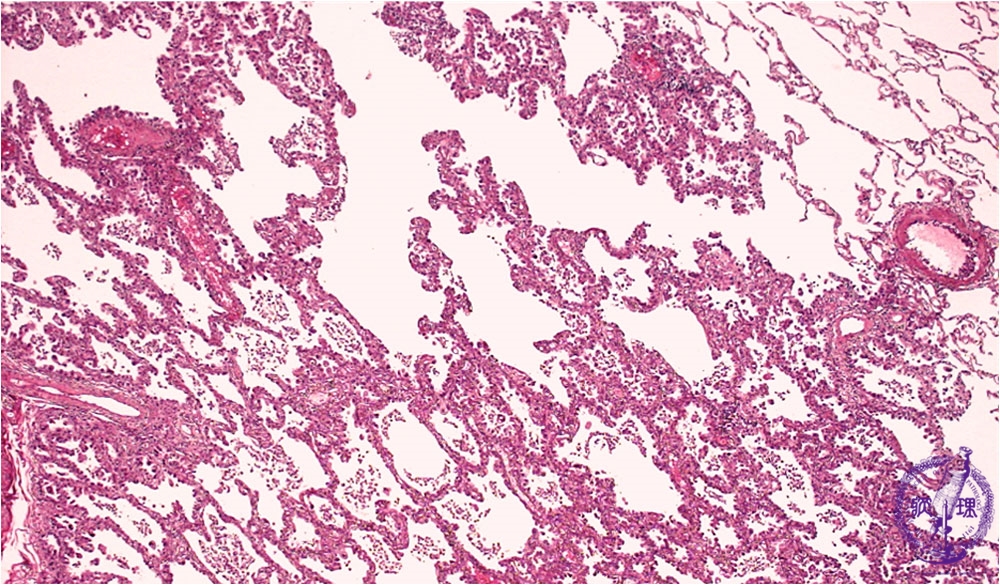

非小細胞肺癌(腺癌)ミクロ像(HE弱拡大)

ミクロ像(HE弱拡大):肺原発の腺癌では初期には既存の肺胞上皮を置換しながら増殖することが多く、細気管支肺胞上皮癌の形態を呈する。